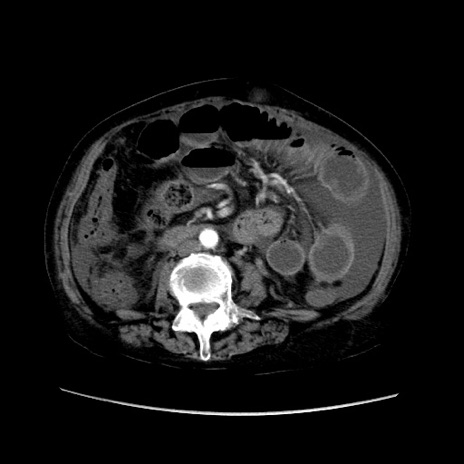

症例31(横断像)

【症例】80歳代 女性

【主訴】腹部膨満感

【現病歴】他院にて肝硬変にてフォロー中。1週間前から便秘、腹部膨満感、臍部腫瘤あり受診となる。

【既往歴】肝硬変

【身体所見】腹部膨隆あり、皮膚変化なし、疼痛なし。

【データ】WBC 4600、CRP 0.25